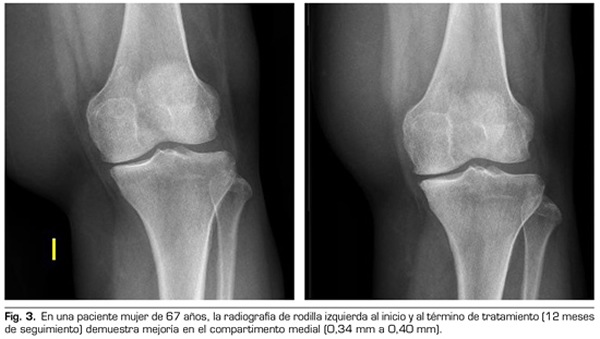

Con respecto a las variables radiológicas, al valorar a 53 de los 115 pacientes que cumplieron un año de seguimiento después del tratamiento con ozono, se observó que el compartimento interno aumento significativamente de 4,12 ± 1,41 mm a 4,4 ± 1,35 mm (p = 0,0008) y el compartimento externo aumentó de 6 ± 1,37 a 6,16 ± 1,4 mm (p = 0,0753) (Tabla II). Se presentan 2 casos clínicos como muestra del cambio radiológico en los compartimentos interno y externo (Figuras 2 y 3).

Tras un año de seguimiento con controles radio-lógicos a 53 de los 115 pacientes del estudio, el ozono (O2-O3) ha sido capaz de aumentar el mínimo espacio articular del compartimento medial (de 4,12 a 4,44 mm) y del compartimento lateral (de 6,0 a 6,16 mm), revirtiendo la artrosis de rodilla en nuestra serie de casos. Este hallazgo sugiere el efecto modificador de la enfermedad del ozono (O2-O3) sobre la artrosis de rodilla, hallazgos que coinciden con lo reportado recientemente por Fernández-Cuadros y cols. (9).